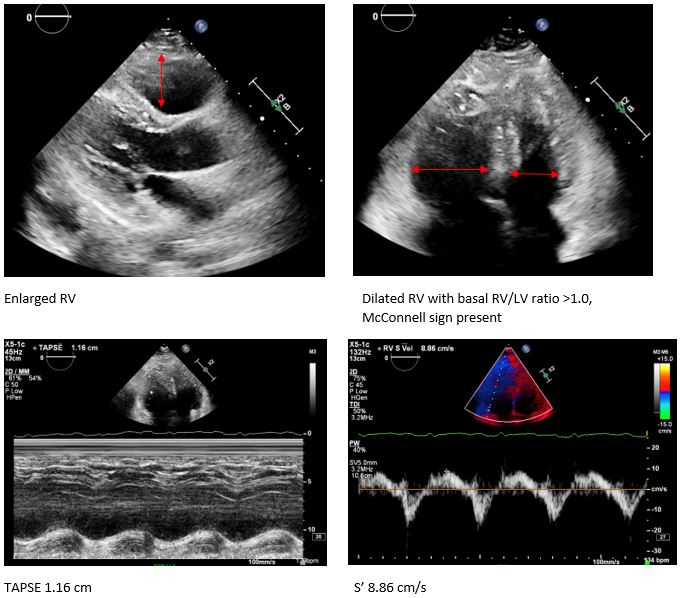

Her troponin T and D-dimer levels were both significantly elevated, at 289 pg/mL (normal < 14) and 3195 ng/mL, respectively. An ECHO revealed signs of right ventricular (RV) overload and dysfunction. Given the high clinical suspicion for pulmonary embolism, she was sent for a CT pulmonary angiogram, which confirmed a massive bilateral pulmonary embolism (PE). She was classified as Class V on the Pulmonary Embolism Severity Index (PESI) and diagnosed with intermediate-high risk PE.

Case Summary